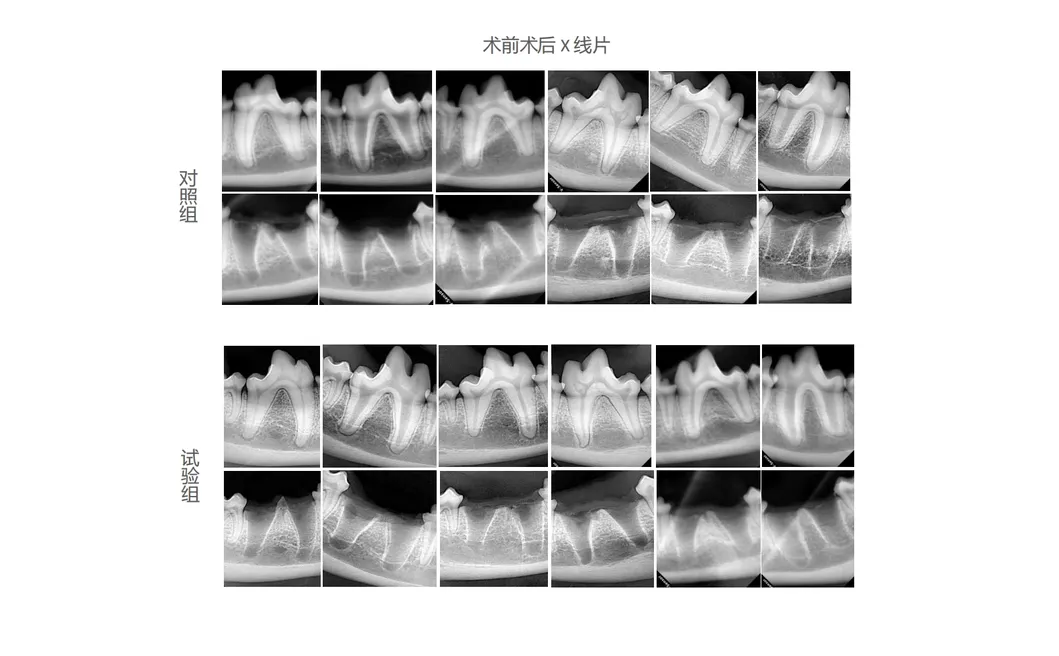

In this groundbreaking study, subjects were meticulously chosen to analyze the effectiveness of next-generation dental tools. A control group used traditional manual extraction devices, while a treatment group utilized the revolutionary Pneumatic Dental Elevator Kit. Researchers conducted exhaustive observation on physiological parameters, intraoperative complications, extraction duration, and socket damage levels.